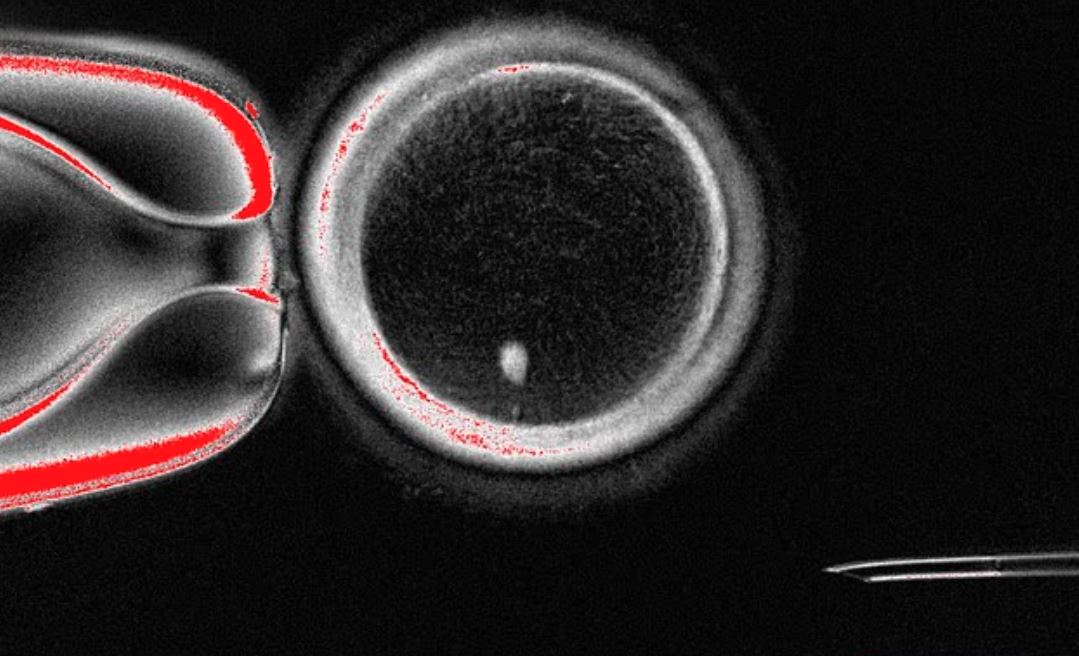

실제 실험에서, 이렇게 만들어진 82개의 인공 난자를 수정시킨 결과, 약 9%가 초기 배아 단계인 '배반포'까지 성공적으로 발달했다고 합니다.

▪ 안전성 문제 : 성공적으로 발달한 소수의 배아에서도 '염색체 이상'이 발견되었습니다.